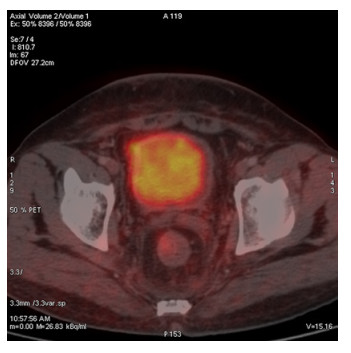

Abstract: Rectal malignancy is usually symptomatic due to its location, and most of the time presents with pain and bleeding due to its growth and ulceration. It is difficult to identify the primary as carcinoma or lymphoma based on symptoms only, as both have a similar presentation. As it presents the rarest form of histology, non-Hodgkin's lymphoma in the rectum is still difficult to diagnose initially, and its treatment is debatable. We describe the case of a 49-year-old male from Bangladesh with the same presentation. His treatment was delayed for more than a month as immunohistochemistry and staging delayed the final diagnosis. The disease was diagnosed as stage IE with the help of a positron emission tomography (PET)-CT scan, and due to the local progression the patient had a massive rectal bleeding that needed an urgent intervention. Radiotherapy was applied to stop the bleeding. Hypofraction followed by a conventional fraction of external beam radiotherapy (EBRT) with a total of 40 Gy was applied. Post-EBRT digital rectal examination showed no residual except scaring, and a PET scan was also negative for residual disease. Due to uncertainties and lack of any precious guideline, 6 cycles of adjuvant chemotherapy with the R-CHOP schedule were also completed. Without surgery, the combination of EBRT and chemotherapy helped to preserve the organ, and the patient has been disease free for more than 2.5 years since his treatment.